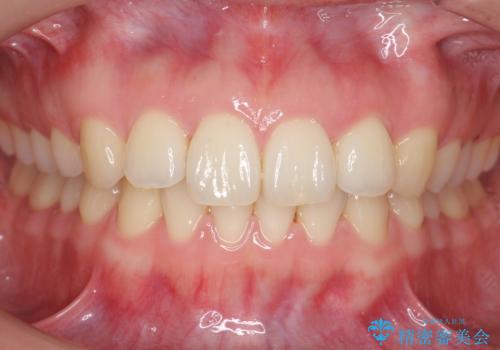

顕著な八重歯をインビザラインで治せるところまで改善